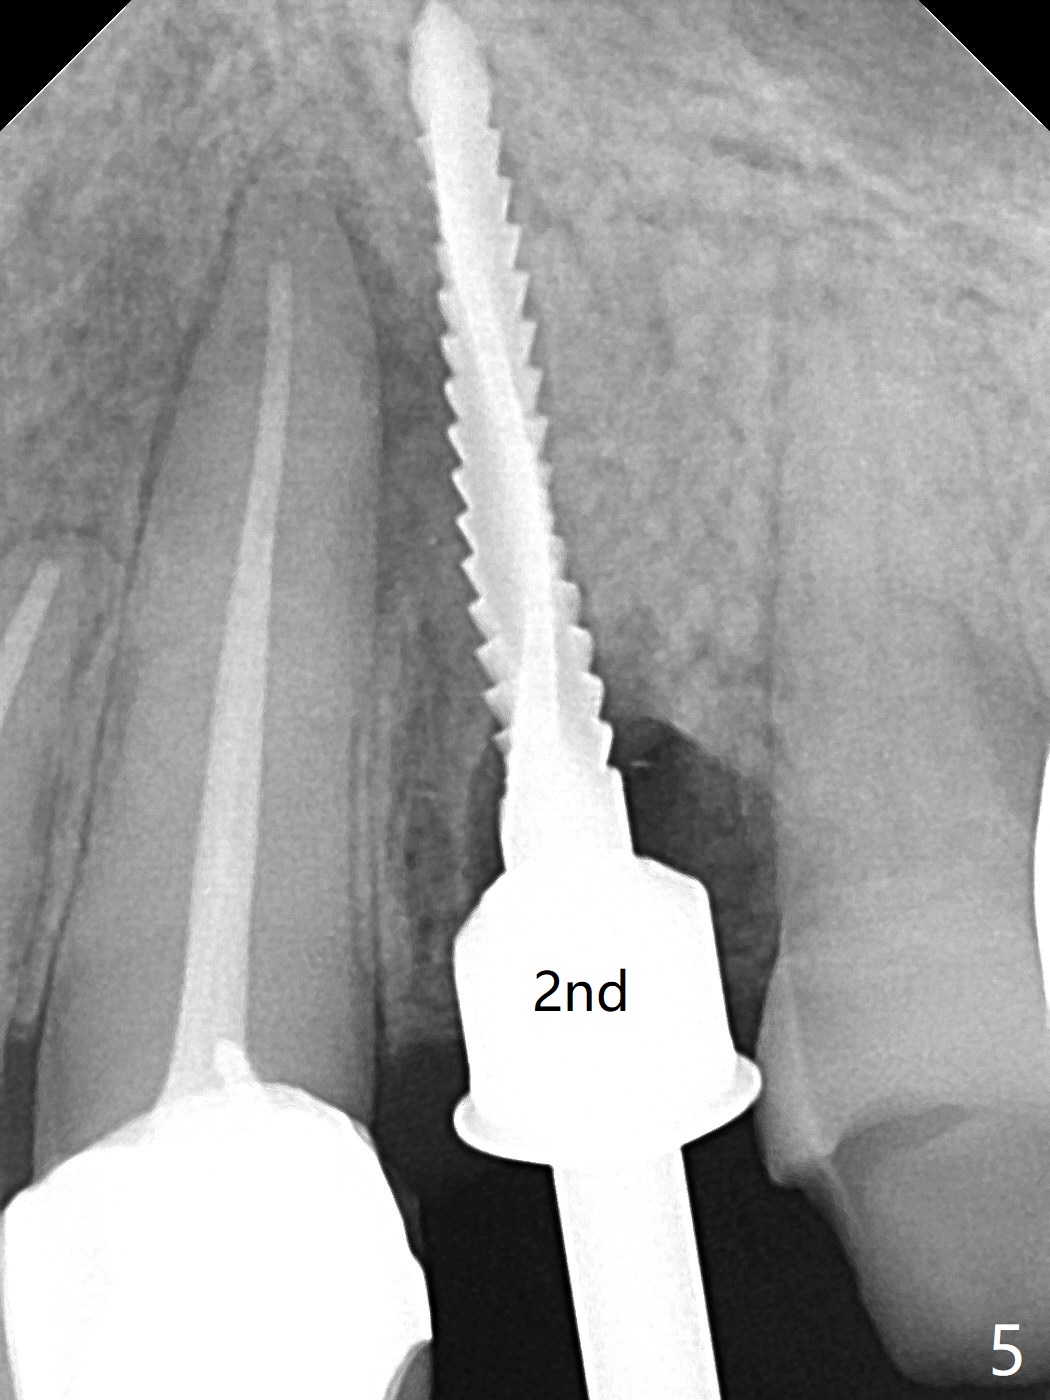

68岁女左上4颊侧瘘道(图一:*),与根尖颊侧骨板缺失相通,其实腭侧根尖周围病变更大(也与颊侧窝相通),术中没有注意腭侧根接近3(图二:P),稀里糊涂的基本顺着腭侧根(颊侧)走向钻洞(图四,与图三理想方向对比),突然记起术前设计钻洞必须在腭侧牙槽窝远中颊侧,在远中建立新洞眼(图五),之后无法再次建立新洞眼,只好利用同一个侧面切割钻头将钻洞往远中移位,同样效果不佳(图六),最后只好放弃,放置粘性骨粉(图七:*),覆盖PRF膜,6个月胶原膜,PGA缝线,牙周胶水。术后重新分析表明顺着腭侧牙槽窝种植与尖牙还是有分离(图八,九:*),因为牙槽窝是斜型的(图十:黑色),不过离颊侧骨板也接近(图八:B)。所以钻洞必须斜型针对远中骨壁,表浅些(图十一:红色箭头);一旦进入骨板,改变角度(图十二:红色箭头),适当矫枉过正,随着植体增大,钻洞会往近中偏移(白色箭头)。最好植体方向理想(图十三)。不过植骨后钻洞偏移可能性比较少。缝线和牙周胶水似乎是一个稳妥固定胶原膜方法。术后病人抱怨水肿严重,术后八天颊侧根尖隆起是由于骨粉推出骨板之外(图十五,十六:*),上颌窦底板无意穿孔(^)伴有上颌窦膜(M)增厚,与术前对比(图十七:上颌窦窦腔清晰)。术后一个月6个月吸收膜不见了,大多数缝线已经脱落,最后两根缝线撤除后,牙槽窝开口已经关闭,好像主要成分是骨粉(图十八)。术后5个月牙槽嵴宽,角化龈也宽,好像可以植入4x11.5毫米植体(图十九)。